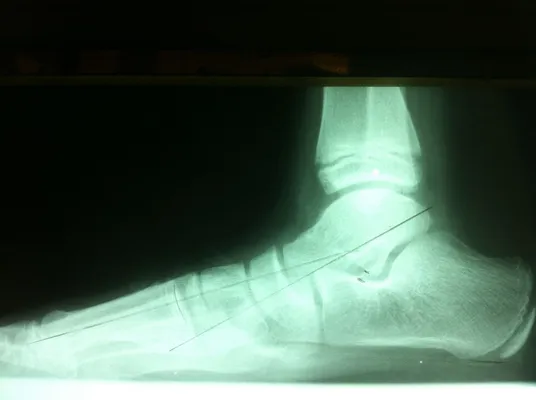

Below are x-rays of a foot pre-operatively (left) where the black line indicates and plantarflexed (downward directed) talus bone and post-surgical repair with a subtalar joint implant and lenthening of the calf muscle which allows the calcaneus (heel bone) to set underneath the talus and the implant keeps the talus from subluxing off the calcaneus and now the talus is more inline with the front of the foot (right).